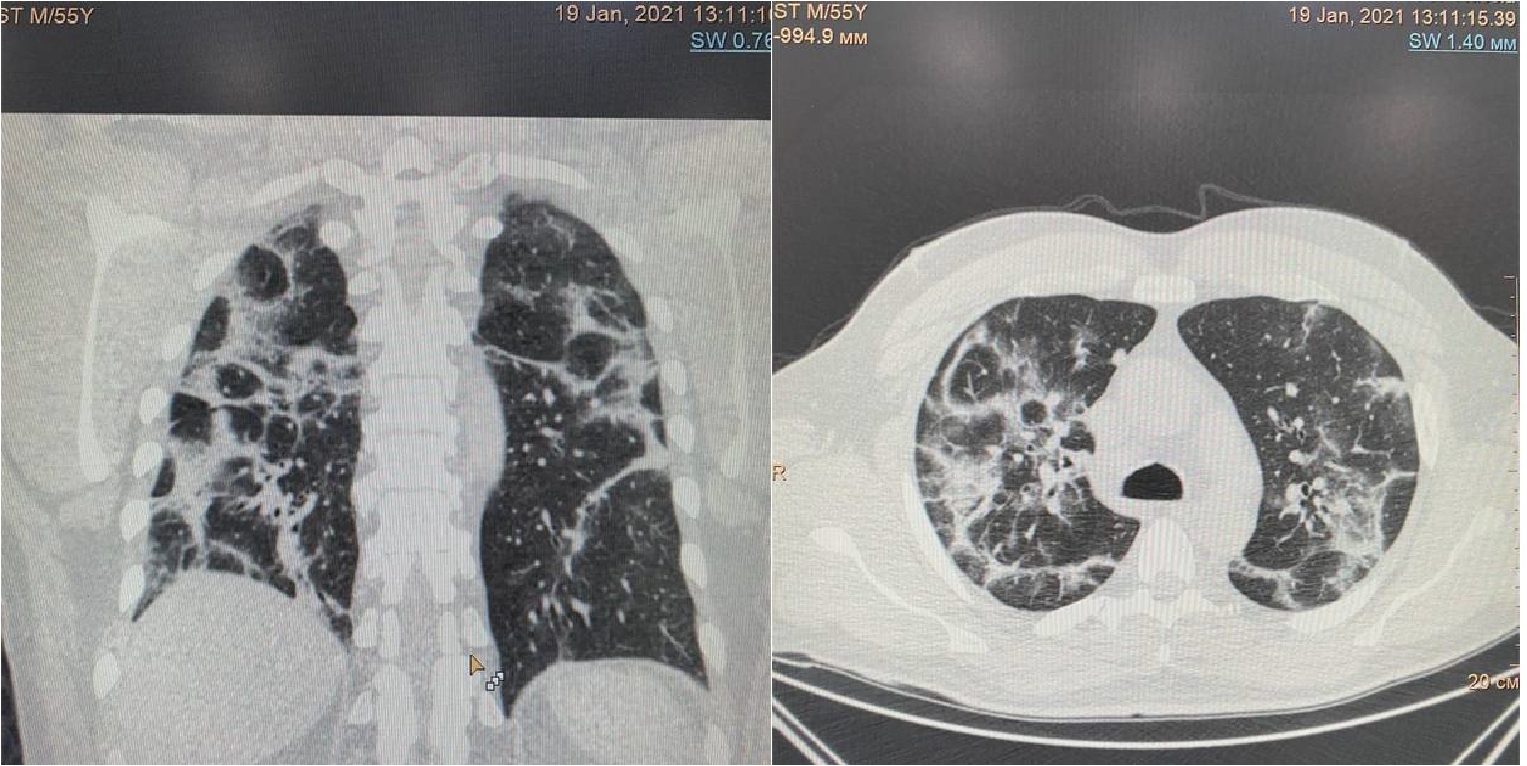

На 16 сутки госпитализации пациент начал жаловаться на резкое усиление одышки даже в покое, невозможность находиться в прон-позиции. МСКТ органов грудной клетки обнаружила уменьшение объема поражения легких до 30%, также был впервые выявлен спонтанный средний правосторонний пневмоторакс (рис. 3).

Рисунок 3. МСКТ органов грудной клетки – признаки двусторонней полисегментарной интерстициальной пневмонии (объем поражения 30%, КТ-2). Средний правосторонний пневмоторакс (красные стрелки).

Появлению данного осложнения не предшествовали какие-либо инвазивные манипуляции в области дыхательных путей, пищевода, пациент не находился ИВЛ. Однако возникновение ПТ коррелирует усугублением дыхательной недостаточности, снижением SpO2 (рис. 4) с пиком ЛДГ (до 397 ед/л), уровень которого прогрессивно возрастал на протяжении всего лечения (рис. 5).

Проведено дренирование плевральной полости справа по Бюлау. В результате отмечена отчетливая положительная динамика в виде устранения одышки, повышения SpO2. Через 3-е суток при контрольной рентгенографии органов грудной клетки выявлен верхушечный пневмоторакс справа (рис. 6), проведена пункция плевральной полости, дренирование продолжено. На фоне устойчивой положительной динамики в дальнейшем, на 23-е сутки терапии пациент выписан в удовлетворительном состоянии.